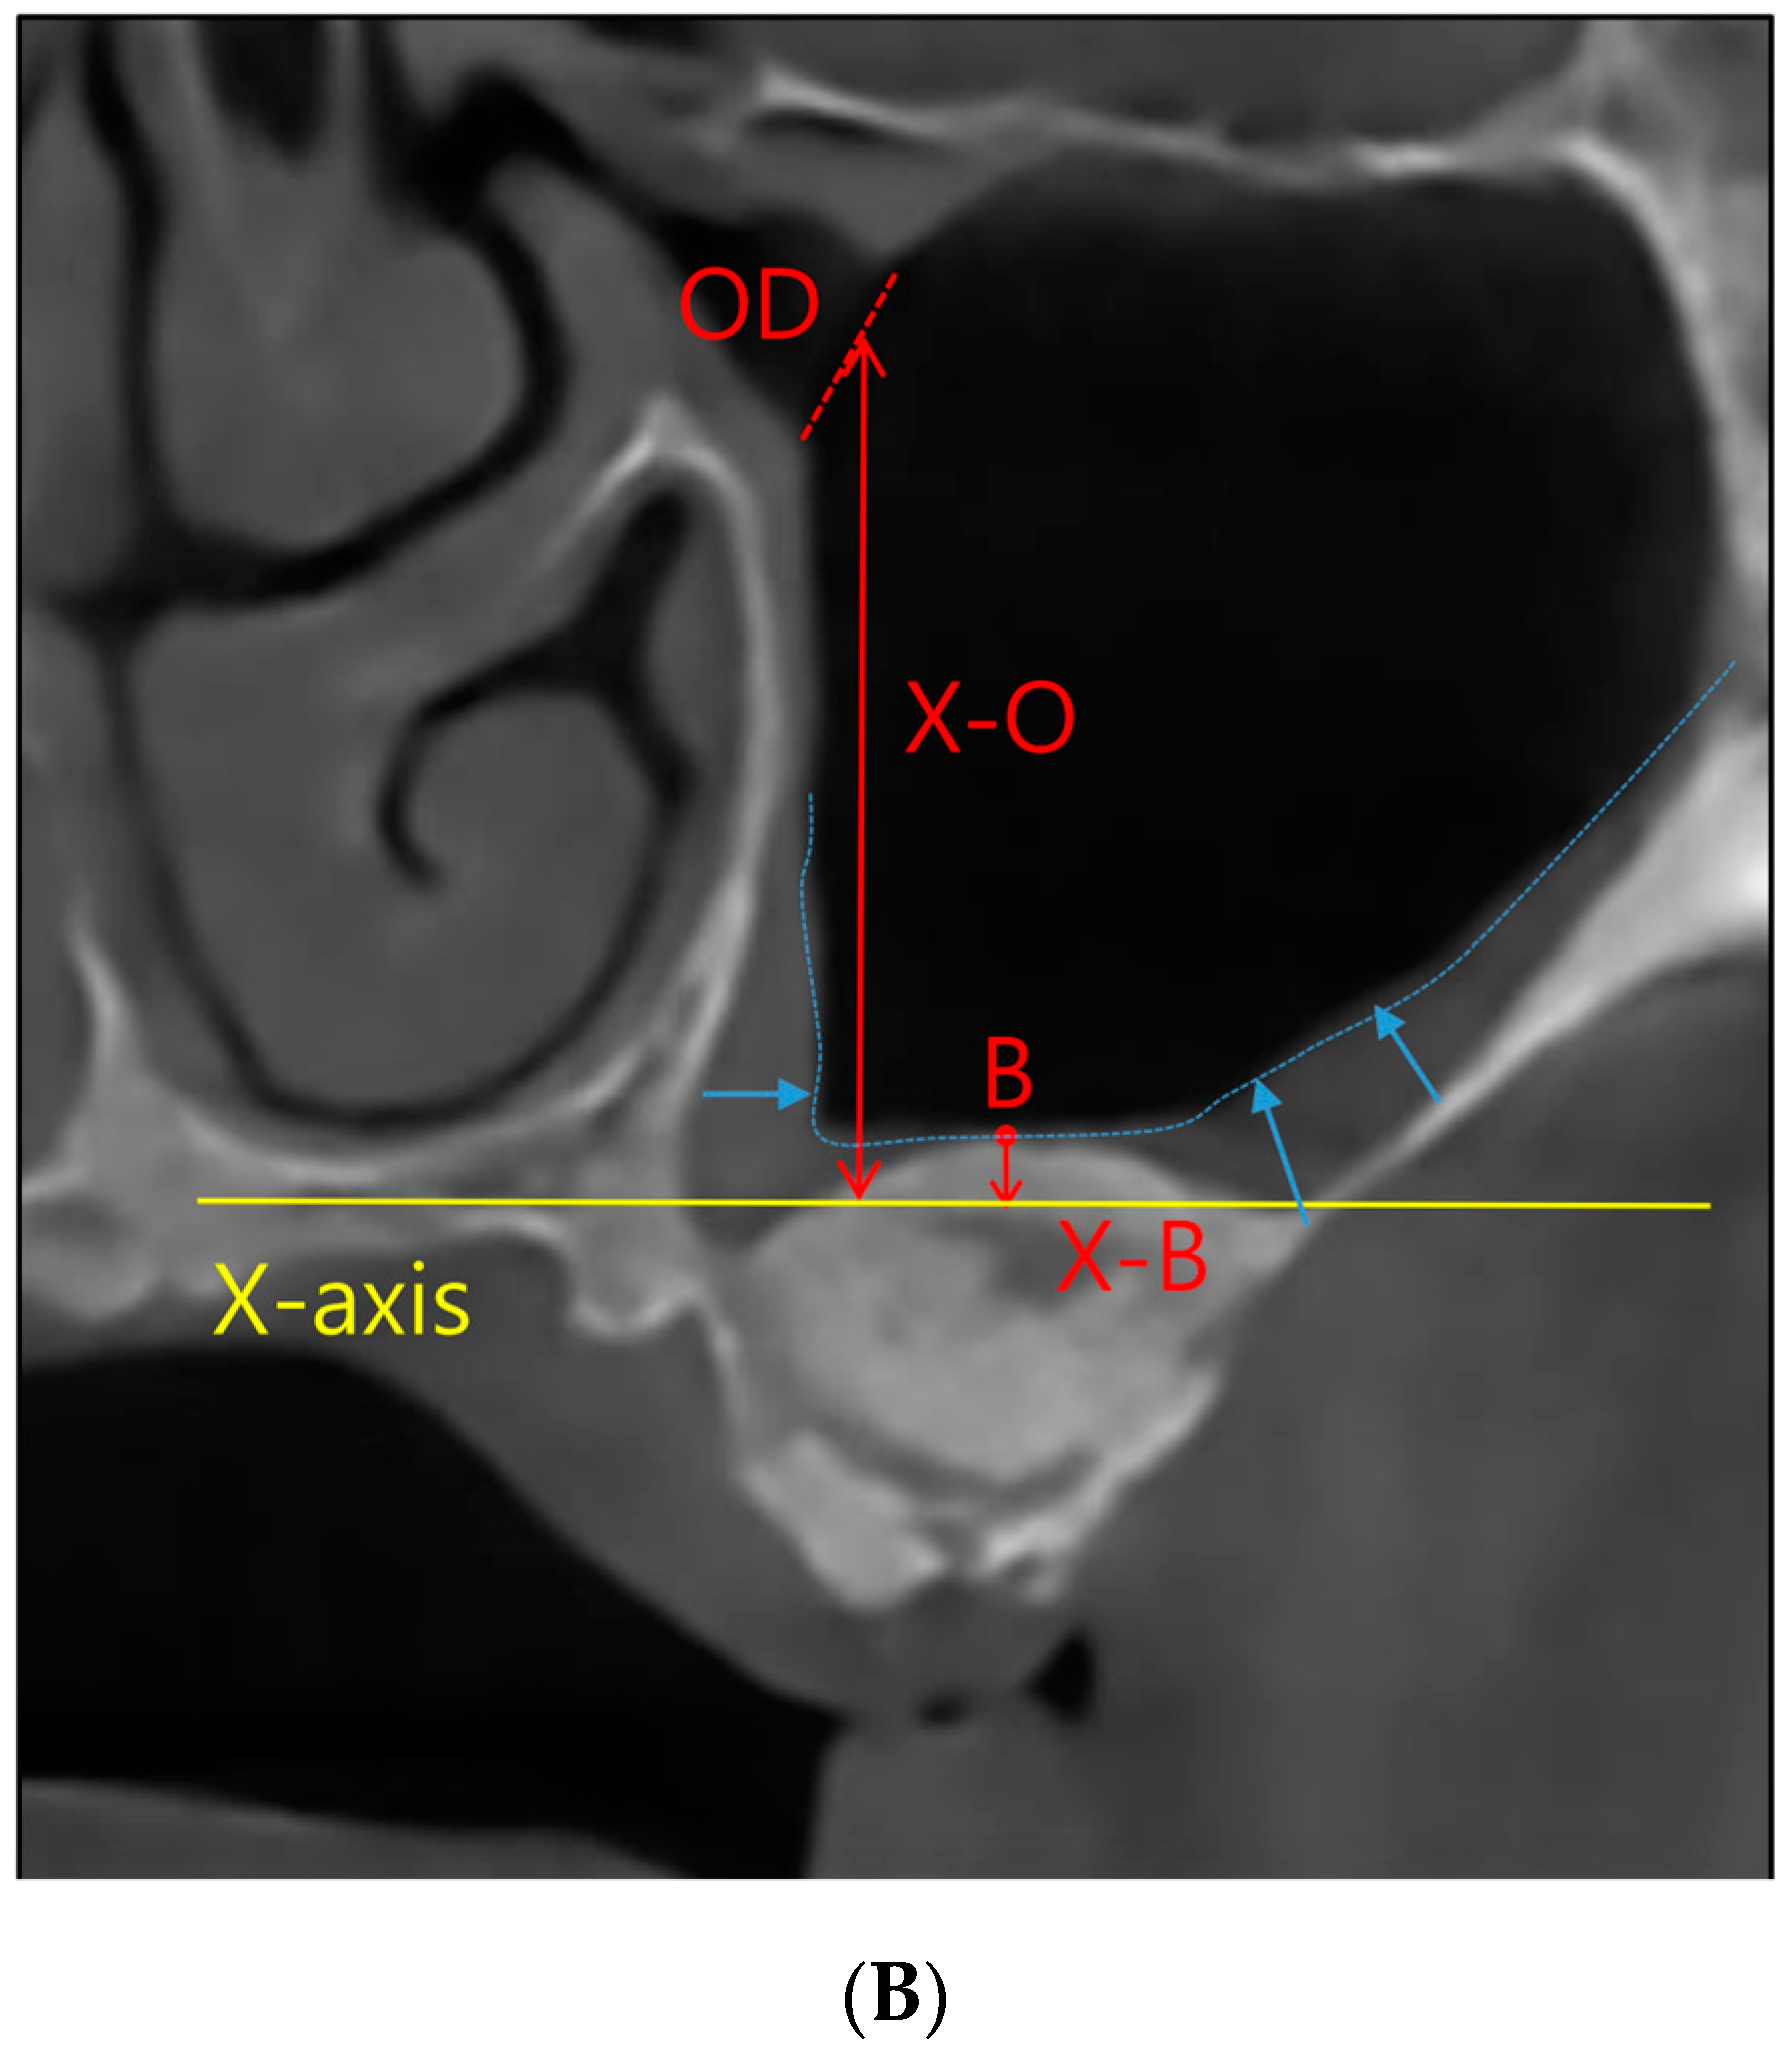

All study participants underwent CBCT imaging both before and after their surgical interventions, with a mean postoperative imaging interval of 7.0 ± 1.8 months. To provide comprehensive procedural descriptions, InVivoDental (Version 6.0.5, Anatomage, San Jose, CA, USA) was employed for acquiring CBCT images. Subsequently, the images were meticulously exported the Digital Imaging and Communications in Medicine (DICOM) files and meticulously loaded them into InVivo software (Version 6.0.5) for precise measurement. Within this software, we ascertained the preoperative and postoperative values for MSMT, MOD, and the ratio of MSMT to MOD (Figure 1).

Figure 1.

Coronal view of cone-beam computed tomographic images of the maxillary sinus. (A) Preoperative view. X-axis, nose floor in coronal view; OD, maxillary sinus ostium diameter; F, the floor of the maxillary sinus; X-F, distance between the X-axis and floor of the maxillary sinus; X-O, distance between the X-axis and maxillary sinus ostium; MSMT, maxillary sinus mucosal thickness; X-F + X-O, maxillary sinus ostium height/distance between the maxillary sinus ostium and sinus floor. (B) Postoperative view of sinus augmentation and bone graft. X-B, distance between the X-axis and sinus augmentation, X-F + X-B, increase in alveolar bone height in sinus augmentation.